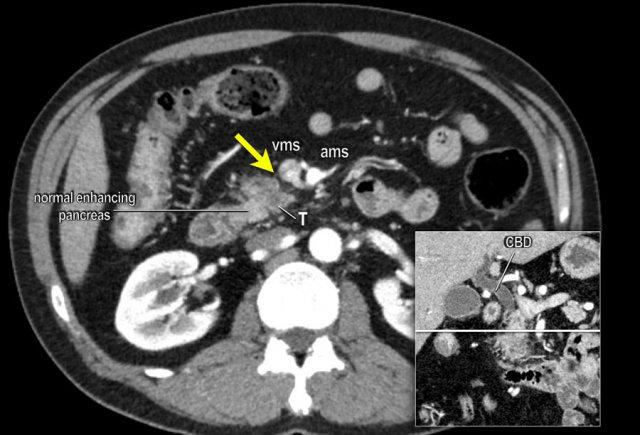

CT axial cho thấy:

- Khối u ở thân tụy (đầu mũi tên trắng).

- Tiếp xúc khu trú < 90º với động mạch mạc treo tràng trên (SMA).

- Tiếp xúc rộng hơn từ 90º – 180º với SMV, SMV bị hẹp nhẹ và biến dạng (mũi tên vàng).

- Giãn ống tụy

Tái tạo mặt phẳng coronal cho thấy:

- Bất thường bờ viền thành SMV được nhận thấy rõ hơn trên tái tạo coronal này (mũi tên).

- Huyết khối trong các nhánh bên của SMV (mũi tên xanh nhỏ).

Tái tạo mặt phẳng coronal cho thấy một khối u lớn xuất phát từ cổ tụy với kiểu phát triển xâm lấn (hình A và B).

Có hiện tượng bao quanh động mạch thân tạng 360º (mũi tên trong A).

CT axial MIP tại mức động mạch thân tạng cho thấy hẹp động mạch gan chung bị bao quanh (mũi tên), rất nghi ngờ xâm lấn.